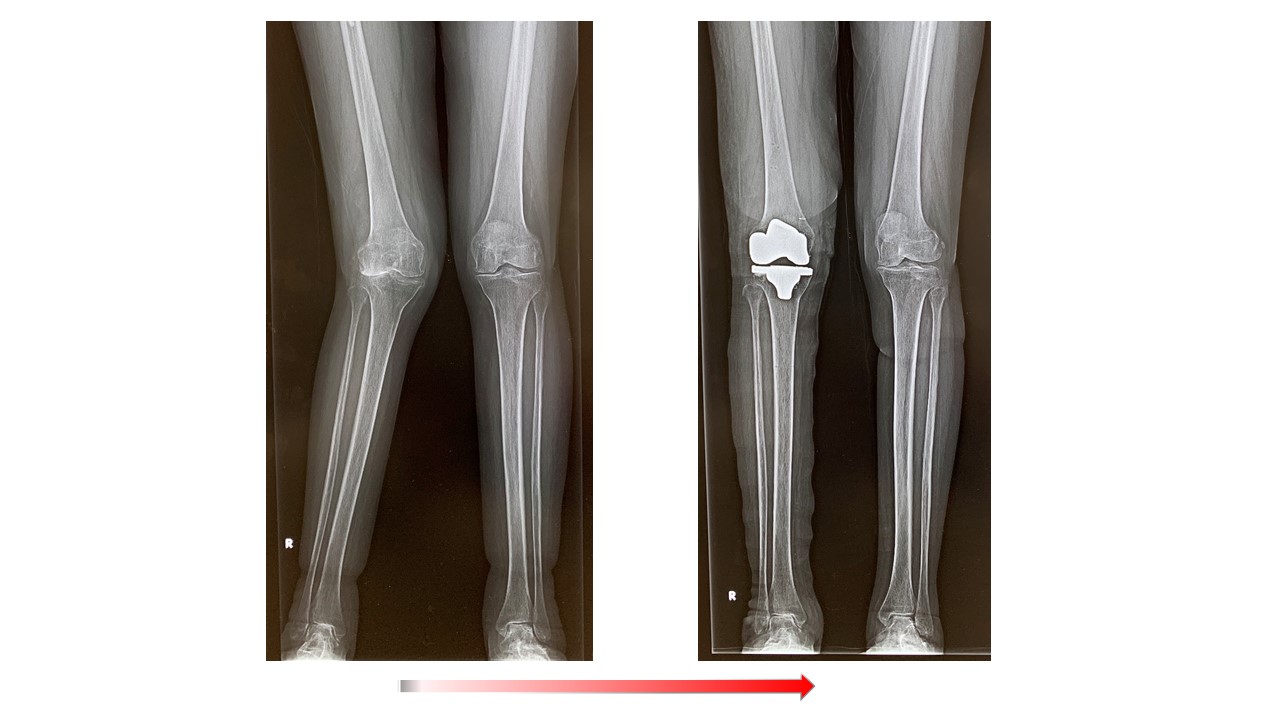

人工膝関節全置換術(単顆置換術)

人工膝関節全置換術(Total knee arthroplasty、TKA)ではナビゲーションシステムを使用して手術を行っています。より良い術後の満足度を得るため、生理的な膝のバランス、アライメントなどを考慮に入れた上で、術中の膝の状態をみながら、最適なインプラントの設置位置を決めて手術を行っています。そのため以前に比べてより使い易く違和感の少ない人工膝の再現が可能になっています。これらの術前検査として、立位での下肢全長のレントゲン検査やMRI検査、骨密度検査等も行いながら、最適なインプラントの選択を行います。さらに長期的には良好な骨の状態を保つことが重要ですので、術後も骨粗鬆症薬等につき外来でフォローアップ致します。紹介受診の場合はかかりつけのクリニックで骨粗鬆症薬の投薬を継続頂いてます。